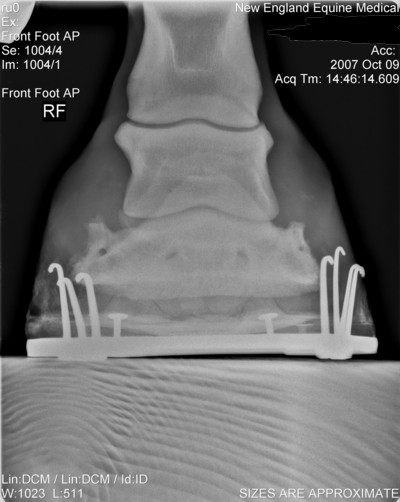

Here are his xrays from about 10-12 weeks ago after the first corrective shoeing. Also included picture of his feet last year before any problems.

Last year

Left AP

Left lat

Right AP

Right Lat

Though I will measure it later, the coffin bone' solar surface angle is acceptable as shod and it should be noted this value does vary greatly among normal horses. Note this is not the same as saying there has been no rotation since the farrier has adjusted the angle with a pad and could have rasped the front wall parallel. We just do not have the information to judge.

Breakover, which is about a cm or two in front of the tip of the coffin bone, looks pretty good though I would prefer a lot more slope to the rocker like that seen in a natural balance shoe. The breakover point of these shoes would disappear on soft ground as the shoe sinks and breakover moves forward to the tip of the foot. Julie would then be right with breakover well too far forward.

Although these images demonstrate the lack of heel and the attempts to correct it, at least the appearance 60 days ago, I would still like to see current images of the foot and sole itself. Your old farrier is correct if the horn quality of the wall is poor and/or the wedges overload the heels. The wedges will distort and breakout poor quality horn and pressure overload slows the growth of the wall at these points. I also do believe egg bars help support poor quality heels when used with proper trimming principles and horn care for more on the trimming see Diseases of Horses » Lameness » Diseases of the Hoof » Correcting Long Toe Low Heel Foot Conformation.